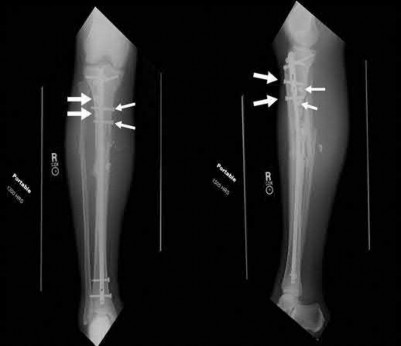

What is the most common type of malalignment after intramedullary nailing of distal 1/3 extra-articular tibia fractures using a infrapatellar approach when compared with plating?

The most common type of malalignment after intramedullary nailing of distal 1/3 extra-articular tibia fractures using an infrapatellar approach when compared with plating is valgus malalignment.

Fixation of distal one-third tibial shaft fractures can be successfully treated with either intramedullary nailing or plating. The literature describes advantages and disadvantages to both approaches, however intramedullary nailing has been shown to lead to increased rates of valgus malunion. Recent studies have shown that using a suprapatellar approach may decrease the incidence of valgus malalignement.

Vallier et al performed a randomized prospective study to compare plate and nail stabilization for distal tibia shaft fractures by assessing complications and secondary procedures. One-hundred and four patients were randomized to either reamed intramedullary nailing, or medial distal tibia plate fixation.

Primary angular malalignment was identified in 17 patients (16.3%). This included four patients treated with tibial plating (8.3%) and 13 patients treated with nails (23%, P = 0.02). Eight of these (7.7% of all patients) had malalignment between 6° and 10° of angulation. Valgus was the most common

angular deformity, accounting for 70% of angular deformity cases.

Avilucea et al. looked at the immediate postoperative alignment of distal tibia fractures (within 5 cm of the tibial plafond) treated with suprapatellar intramedullary nail (IMN) insertion compared with the infrapatellar technique. They found primary angular malalignment of ≥5 degrees occurred in 35 (26.1%) patients with infrapatellar IMN insertion and in 5 (3.8%) patients who underwent suprapatellar IMN insertion. They conclude suprapatellar IMN technique results in a significantly lower rate of malalignment compared with the infrapatellar IMN technique.